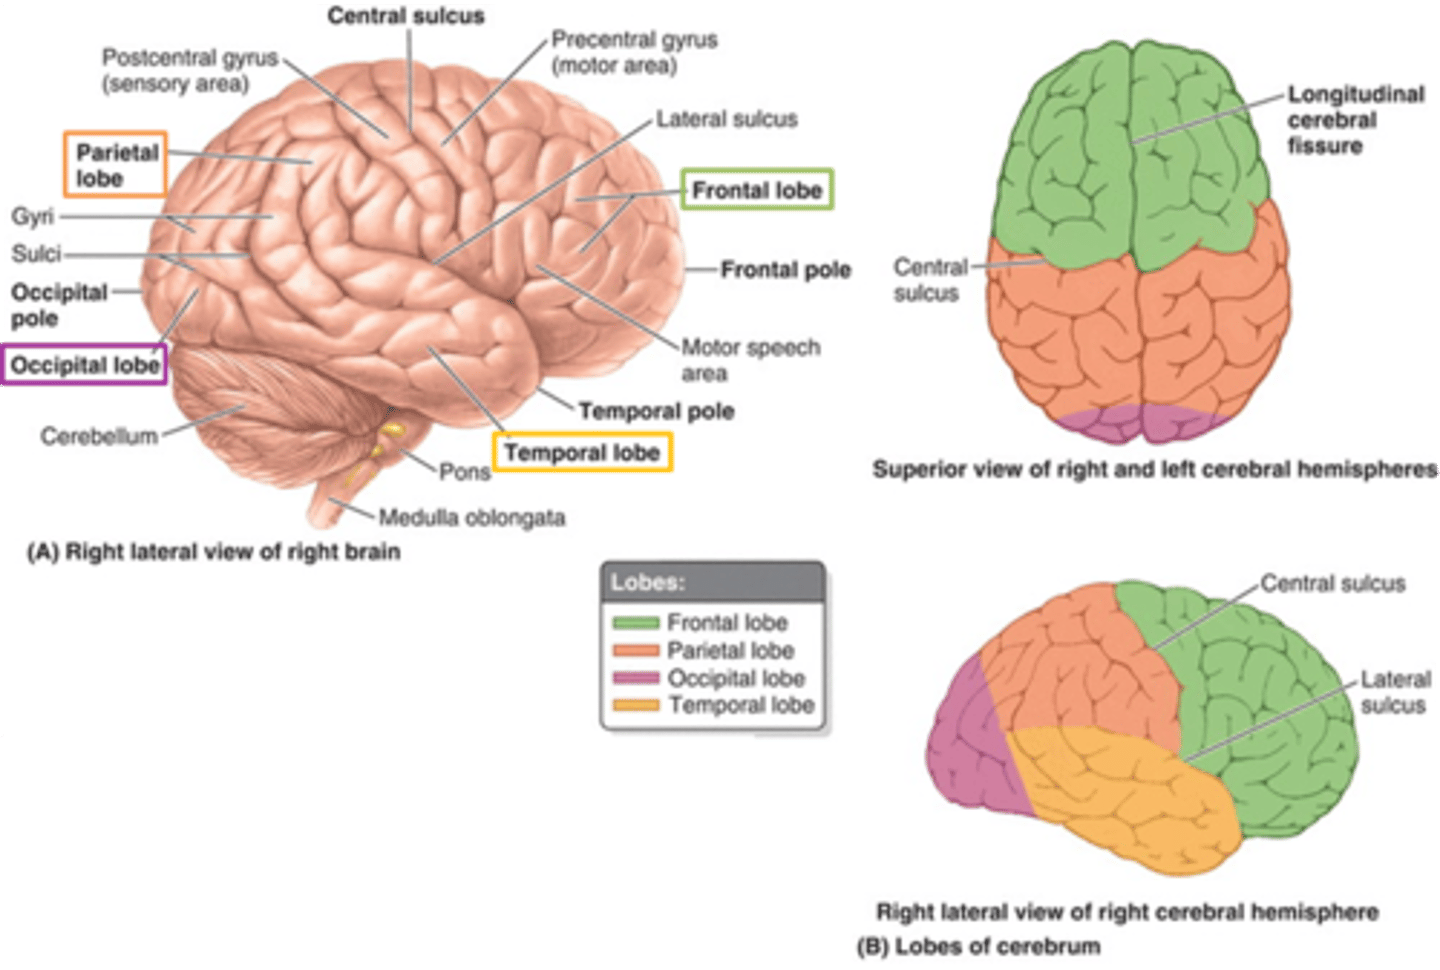

what are the 3 regions of the brain?

1. cerebrum (cerebral hemispheres)

what are the 4 main lobes of the cerebrum?

FPOT

1. frontal

2. parietal

3. temporal

4. occipital

what lobe of the cerebrum is involved with motor and personality?

FPOT

frontal

what lobe of the cerebrum is involved with sensory?

FPOT

parietal

what lobe of the cerebrum is involved in hearing and memory?

FPOT

temporal

what lobe of the cerebrum is involved in vision?

FPOT

occipital

which sulcus separates the cerebral hemispheres?

longitudinal fissure

which sulcus divides the frontal lobe from the parietal lobe and divides the precentral and postcentral gyrus?

central sulcus

which sulcus divides the parietal lobe from the temporal lobe?

lateral (sylvian) sulcus/fissure

which sulcus separates the parietal lobe from the occipital lobe?

parieto-occipital sulcus

which gyrus is the primary motor complex?

precentral gyrus

which gyrus is the primary somatosensory complex?

postcentral gyrus